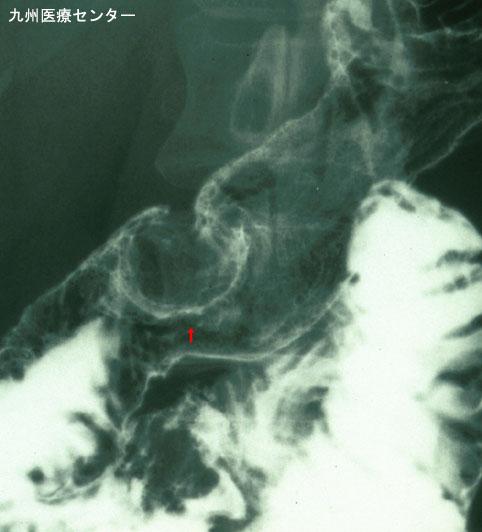

Criteria of Hist.ClassificationMalignant epithelial tumor/Adenocarcinoma

LocationDuodenum/Second portion

Technique, MethodX-ray

Macroscopic TypesType 0/I (Ip) Pedunculated type

Size25 - 29

Depth of Tumor Invasionsubmucosa